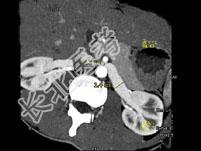

- 多项选择题女,24岁, 发作性肉眼血尿1年,实验室检查: 尿蛋白(-~+)、红细胞(1~2/HP),尿蛋白直立试验(+), CT扫描如图,下列说法正确的是 ( )

B、左肾静脉走行至肠系膜上动脉与腹主动脉间变细,近左肾处扩张

C、左侧肠系膜上动脉与腹主动脉夹角变小

E、考虑为左肾静脉胡桃夹综合征